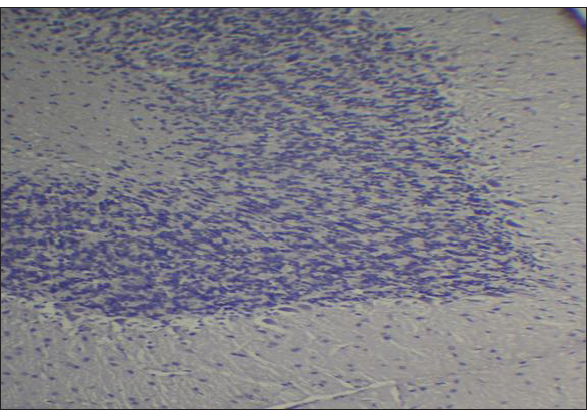

Fig. 2. Effect of gemcitabine, gemcitabine + ALC (25 mg/kg/bw), and gemcitabine + ALC (300 mg/kg/bw) on serum AChE. Histological resultsAccording to the histological investigation, the central nervous system did not contain any beta clusters. The experimental beta-amyloid turns red because it is stained using the pigment Congo red, indicating that the central nervous system is secure from beta-amyloid buildup in the absence of treatment (Fig. 3). The gemcitabine group showed an increase in beta-amyloid accumulation in the rat’s brain, which is stained in red color as shown in Figure 4. However, compared to the gemcitabine group, rats administered gemcitabine plus ALC (25 mg/kg/bw) showed a significant reduction in the buildup of beta-amyloid in the rat’s brain, as depicted in Figure 5. Furthermore, as illustrated in Figure 6, rats treated with gemcitabine + ALC (300 mg/kg/bw) exhibit a significant reduction in the buildup of beta-amyloid in their brains when compared to rats treated with gemcitabine + ALC (25 mg/kg/bw).

Fig. 3. Photomicrograph of the control group’s brain section showing the normal histological architecture without the accumulation of beta-amyloid (congo red, 4×).